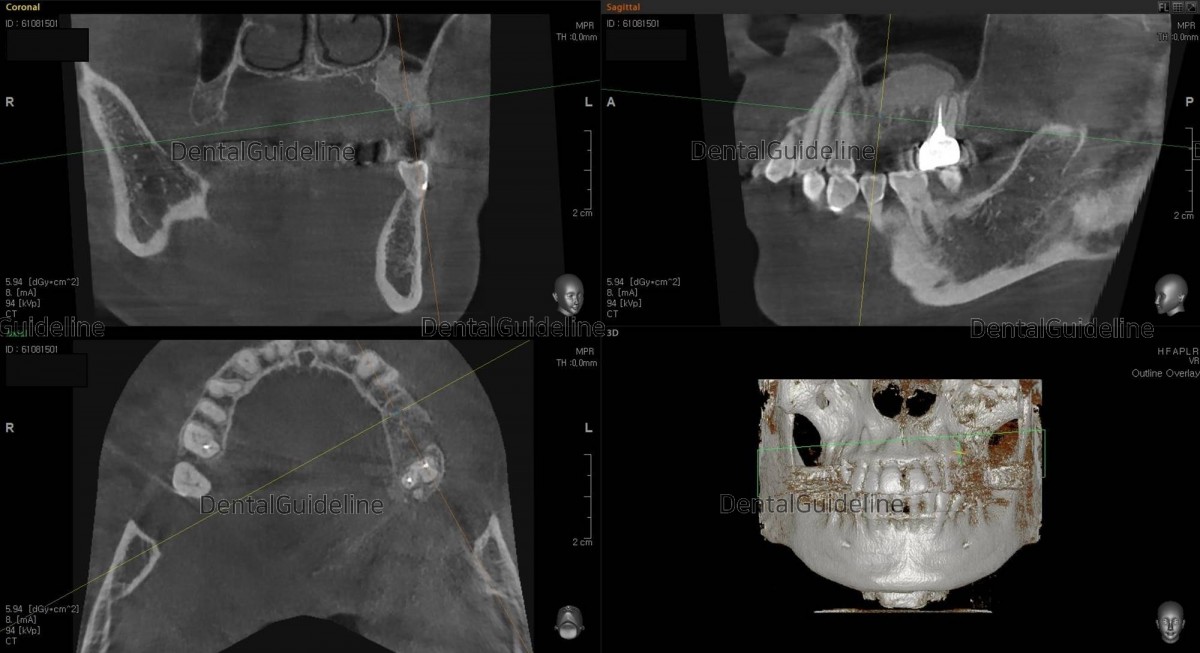

3 CBCT scan image after laterally approached sinus graft.